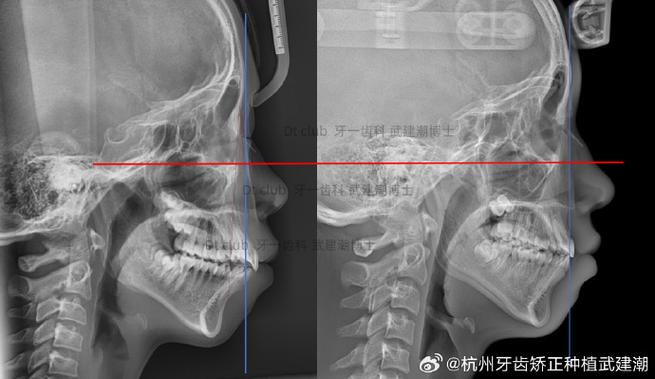

- X线片:薛氏位片(髁突-关节窝侧位像)观察髁突在关节窝内的位置;曲面断层片评估全口牙列与颌骨关系。

- CBCT:三维重建关节结构,精确测量髁突位置、关节窝形态及骨质变化。